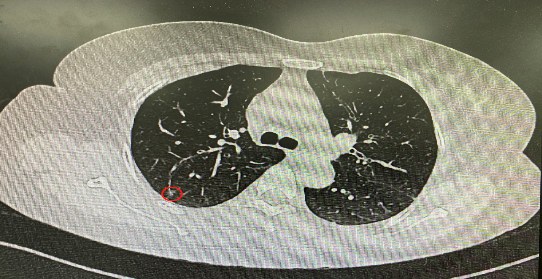

今年54歲的李女士(化名)7月初突然出現(xiàn)右上部腹痛,起初并未在意,以為稍作休息就會(huì)好轉(zhuǎn),但疼痛卻并未消退,持續(xù)了一個(gè)星期。李女士實(shí)在難以忍受,才在家人陪伴下來(lái)到西安國(guó)際醫(yī)學(xué)中心醫(yī)院就診。胸外科二病區(qū)崔凱主任接診患者后,詳細(xì)詢問(wèn)病情并查閱檢查資料,經(jīng)胸部HRCT檢查,結(jié)果提示:右肺上葉后段混合密度結(jié)節(jié)影,考慮原位癌可能,即將患者收入胸腔外科二病區(qū)住院治療。

經(jīng)與患者家屬溝通,崔凱主任決定行外科手術(shù)治療。為達(dá)到精準(zhǔn)切除,術(shù)前需進(jìn)行肺小結(jié)節(jié)切除前定位。由于結(jié)節(jié)位于右肺上葉后段,傳統(tǒng)經(jīng)胸外穿刺術(shù)無(wú)法抵達(dá)病灶。崔凱主任與呼吸內(nèi)科一病區(qū)歐陽(yáng)海峰主任討論后,決定擬行LungPro全肺診療導(dǎo)航下染色定位。即術(shù)前通過(guò)Lung Pro導(dǎo)航規(guī)劃染色位置,經(jīng)Lung Pro實(shí)時(shí)引導(dǎo)支氣管鏡抵達(dá)既定位置,注入亞甲藍(lán)染色劑標(biāo)記結(jié)節(jié)位置。

使用術(shù)前規(guī)劃系統(tǒng)重建全肺3D模型,并于外科醫(yī)生討論染色位置,最終確定標(biāo)記染色點(diǎn)—右肺上葉后段b亞段(RB2b)。術(shù)中使用P290(4.9mm外徑)標(biāo)準(zhǔn)支氣管鏡,根據(jù)導(dǎo)航術(shù)前規(guī)劃路徑,Lung Pro實(shí)時(shí)導(dǎo)航下,GS鞘管進(jìn)入RB2b遠(yuǎn)端官腔外病灶并注射亞甲藍(lán)染色劑。

一切準(zhǔn)備就緒,7月15日,崔凱主任團(tuán)隊(duì)聯(lián)合歐陽(yáng)海峰主任團(tuán)隊(duì)為患者行單孔胸腔鏡下右肺上葉后段切除術(shù),手術(shù)用時(shí)128分鐘順利完成。進(jìn)入胸腔后,亞甲藍(lán)染色部位明顯,患者發(fā)生癌變的右肺上葉后段被成功切除。術(shù)后標(biāo)本根據(jù)染色部位迅速找到結(jié)節(jié),剖開(kāi)位置兼染色位置和病灶完全符合,行術(shù)中冰凍后快速送病理檢查。經(jīng)術(shù)后病理檢查,明確診斷為(右肺上葉)原位腺癌。